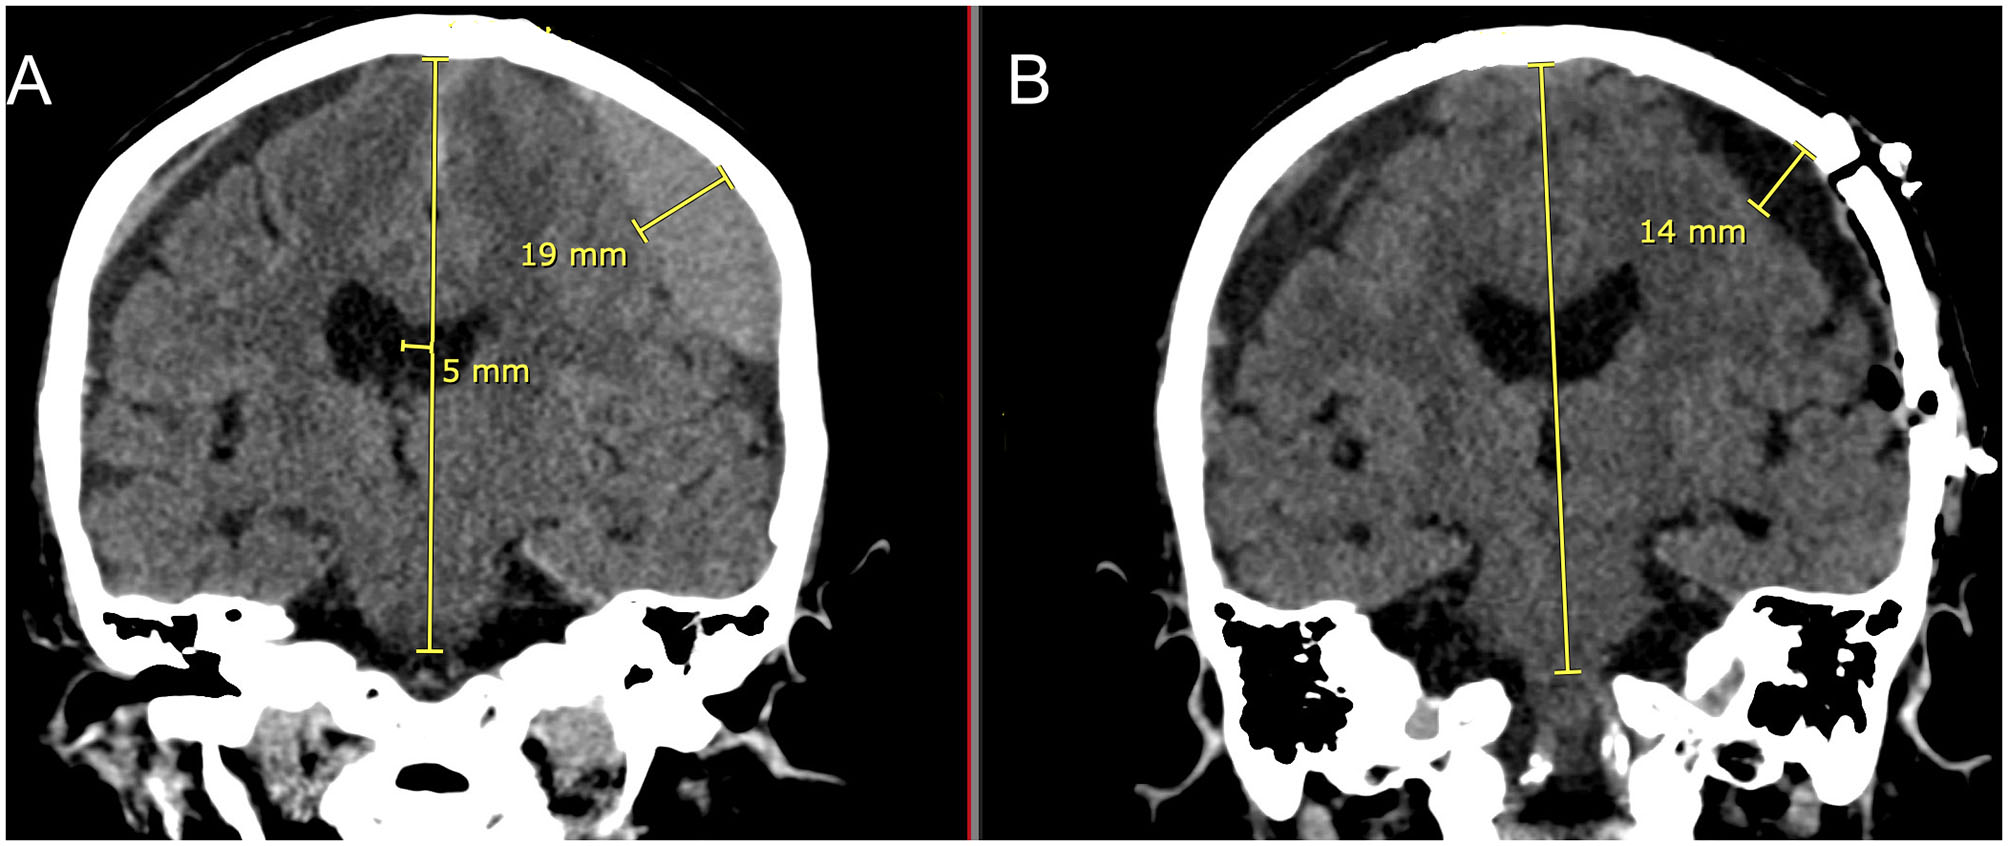

Figure 8 is a demonstration of an 83 yo patient with a cSDH that had very nice expansion of the brain after craniotomy and fenestration within 1–2 h of the surgery. In the post-operative CT scan, there is very little intracranial air seen as every effort was made to fill up the entire subdural space with normal saline irrigation during closure. This is particularly important to allow the brain to re-expand in a liquid medium (36).

Figure 8

Eighty three yo F who suffered a ground level fall who was on aspirin. She had mild headaches and speech difficulties with a right upper extremity pronator drift. (A): Preoperative coronal CT scan demonstrating a left sided cSDH with midline shift. Note the lentiform shape afforded by the inner subdural membrane that is displacing the underlying cortex. There is a smaller right sided acute on chronic SDH. (B): Post-operative coronal CT scan done within 1–2 h of reaching the recovery room. Note the decrease in the mass effect and midline shift with near complete removal of the cSDH and re-expansion of the brain on the left. There is very little intracranial air. On the right sided there is increased prominence of the subdural space and the acute on chronic subdural hematoma.